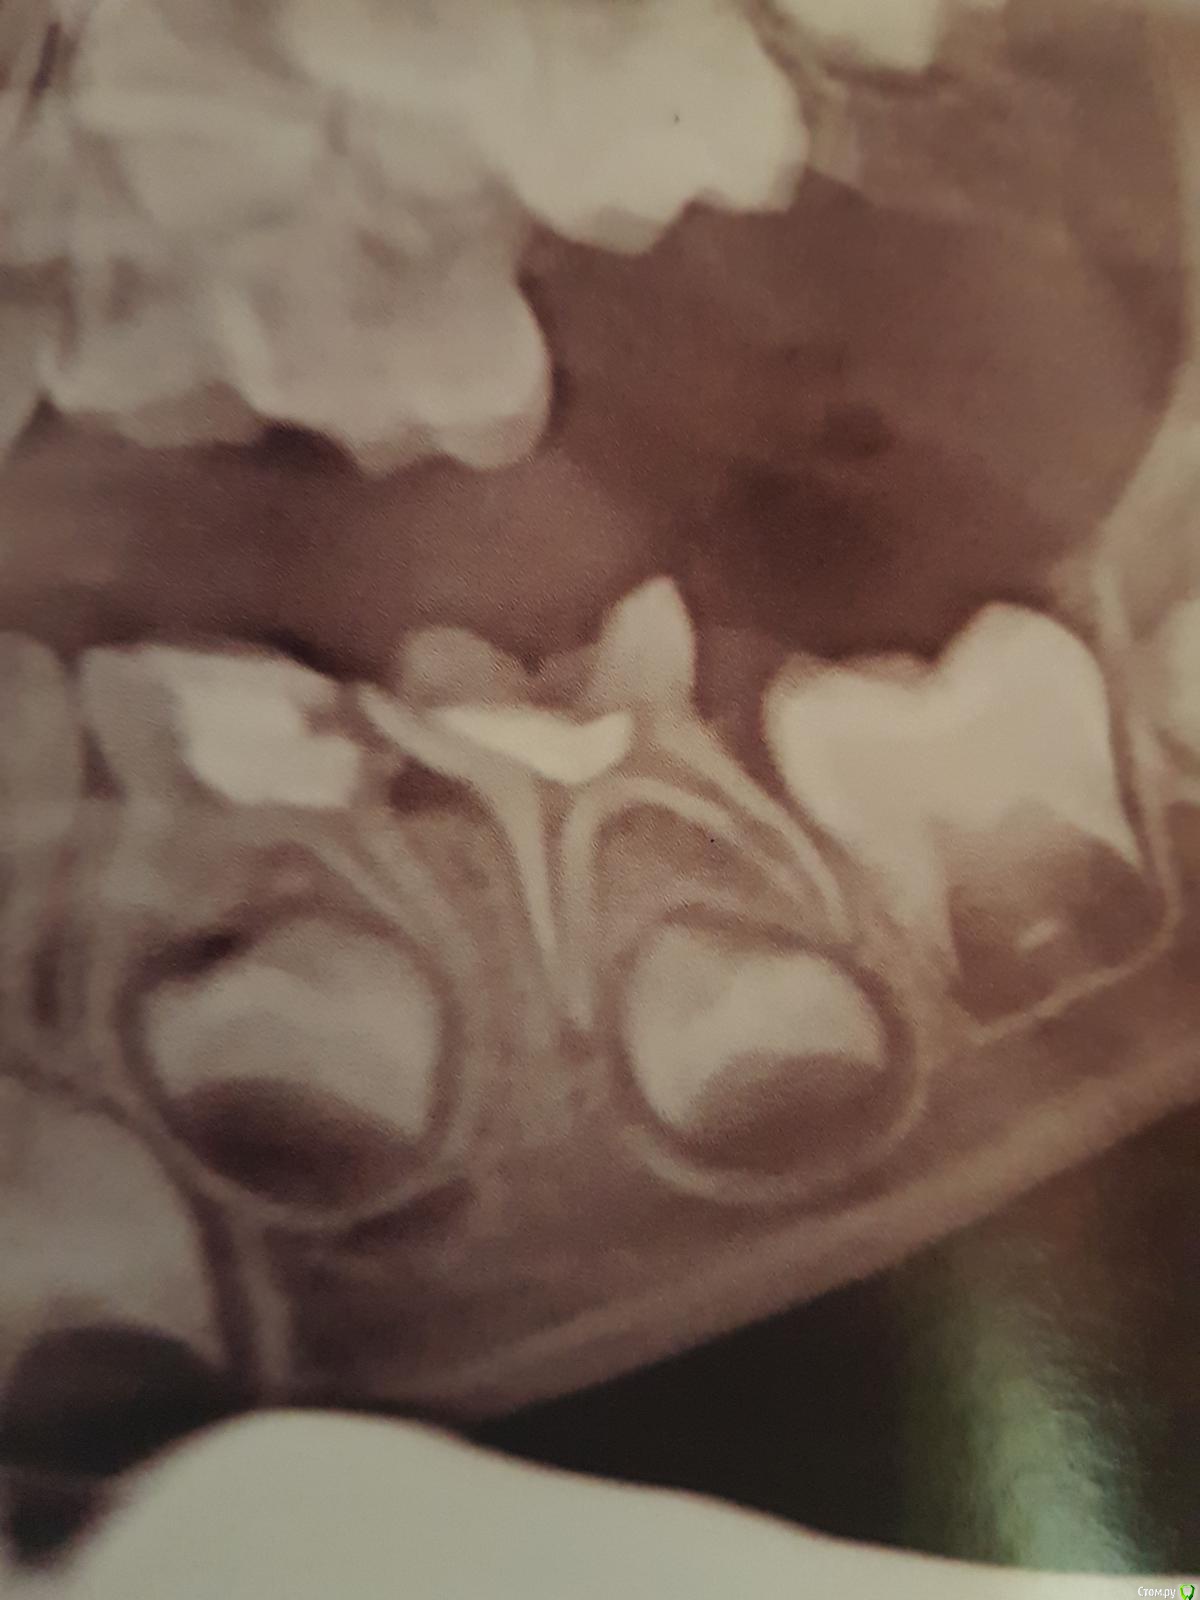

Несколько дней назад ночью этот зуб заболел, дали Нурофен. На утро все прошло. Поехали в стоматологию, сделали ортопантомограмму. Диагноз - периодонтит. На снимке видно воспаление. Тактика лечения - раскрыть каналы, промыть, заполнить полость жидким кальцием на две недели, затем запломбировать каналы, поставить пломбу и накрыть ее коронкой.

Этот врач посмотрел на зуб и сказал - только удаление, зуб уже имеет некоторую подвижность. На снимке те места, что его коллега идентифицировал как воспаление, он назвал гноем.

post-52768-0-88417800-1507727885_thumb.jpg